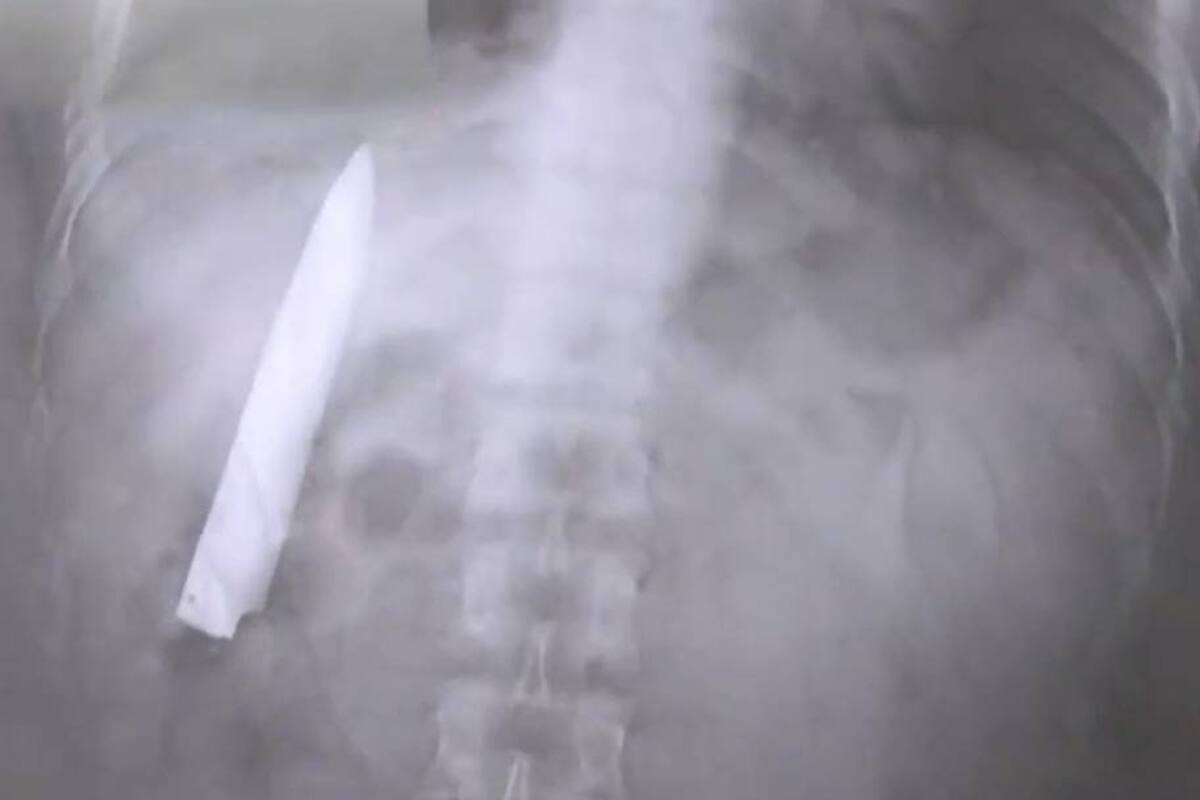

Se hizo una radiografía y le descubrieron un cuchillo en el pecho

Kent Ryan Tomao, de 25 años, es un ciudadano de Filipinas que se realizaba un examen preocupacional el martes pasado cuando de pronto, en medio de las pruebas, los médicos descubrieron en una de sus radiografía que el hombre tenía alojada, en el interior de su torso, una hoja de cuchillo.

Más tarde, los médicos se enterarían de que el joven había sido apuñalado por un grupo de delincuentes 14 meses atrás y, aparentemente, los profesionales de la salud que lo atendieron entonces cosieron la herida dejando la filosa hoja en el interior de Tomao.

El filipino, que fue atacado en la ciudad de Kidapawan cuando circulaba en su motocicleta, según él mismo narró al medio local ABS-CBN, descubrió junto a los médicos el filoso elemento que llevaba en su cuerpo cuando fue a realizarse un examen preocupacional para ingresar a un nuevo trabajo en la provincia de Agusan del Sur.

“Siempre me pregunté por qué sentía algo de dolor en mi pecho cuando el clima es frío, pero no tenía idea de que aquel cuchillazo seguía ahí adentro”, comentó Tomao al citado medio.